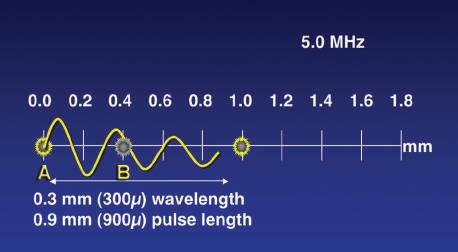

The ability to differentiate two closely situated objects as distinct structures is determined by the spatial resolution of the ultrasound device. Spatial resolution must be considered in three planes, with different determinants of resolution for each. Simplest is the resolution along the axis of the ultrasound beam, or axial resolution. With pulsed wave ultrasound, the transducer introduces a series of brief bursts of sound into the body. Each ultrasound pulse typically consists of two or three cycles of sound. The pulse length is the product of the wavelength and the number of cycles in the pulse. Axial resolution, the maximum resolution along the beam axis, is determined by the pulse length (Fig. 1.25). Because ultrasound frequency and wavelength are inversely related, the pulse length decreases as the imaging frequency increases. Because the pulse length determines the maximum resolution along the axis of the ultrasound beam, higher transducer frequencies provide higher image resolution. For example, a transducer operating at 5 MHz produces sound with a wavelength of 0.308 mm. If each pulse consists of three cycles of sound, the pulse length is slightly less than 1 mm, and this becomes the maximum resolution along the beam

Thus a frequency of 5 MHz can be shown to have a wavelength of 0.308 mm in tissue: λ = c/f = 1540 m/sec × 5,000,000 sec 1 = 0.000308 m = 0.308 mm. Wavelength is an important determinant of spatial resolution in ultrasound imaging, and selection of transducer frequency for a given application is a key user decision.